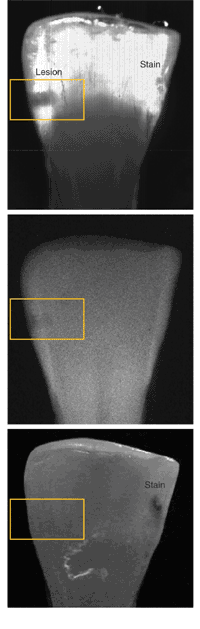

In experiments involving extracted human teeth containing simulated lesions, Fried and his colleagues demonstrated the efficacy of a 1310-nm imaging system for detecting and imaging interproximal caries lesions. The experimental system comprises a fiber-coupled broadband light source (either a 150-W halogen lamp or superluminescent diodes), two crossed linear polarizers for polarization gating, an indium gallium arsenide focal-plane array, and a near-IR camera. A 50-nm-bandpass filter centered at 1310 nm was used to remove all light outside the spectral region of interest. A tooth section of minimal sample thickness (3 mm) was chosen for comparison of the near-IR transillumination system with visible-light fiberoptic transillumination and x-rays; a hole was drilled into each tooth section and filled with hydroxyapatite powder to simulate decay. The near-IR results showed significant contrast between the lesion and the enamel (greater than 0.35) and a spatial line profile that clearly resolves the lesion (see figure). The researchers also worked with thicker samples, up to 6.75 mm, with similar results.1